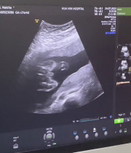

สอบถามรูปอัลตราซาวน์ค่ะ

คุณหมอบอกได้ผู้ชาย จู๋โผล่ คุณเเม่ว่าชัวร์มั้ยคะ ขอดูรูปอัลตราซาวน์เเม่ๆที่ได้ลูกผู้ชายหน่อยค่า

บ้านนี้หมอบอก เด็กผู้ชายค่ะ แต่คุณแม่ก็ไม่มั่นใจเหมือนกันค่ะ..ว่าชายชัวหรือเปล่า😂

หมอบอกว่าได้ผู้ชายค่ะแต่แม่ดูยังไงก็ลูกสาว🥹